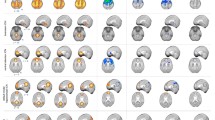

Our exploratory findings showed that, compared with NCs, the PD baseline acquisitions had decreased ReHo in the SMA, the bilateral precentral gyrus, and the bilateral postcentral gyrus [sensorimotor cortex (SMC)], and increased ReHo in the right superior temporal gyrus and right hippocampus (Fig. 2; Table 2). The VBM analysis did not reveal any differences in GM volume and density between the NC and baseline PD acquisitions.

Longitudinal Results

Compared with the PD baseline results, the PD follow-up images showed significantly decreased ReHo in the SMC, DMN (bilateral precuneus, bilateral angular gyrus, bilateral parietal lobule, bilateral middle frontal lobule, and anterior cingulate cortex), and left cerebellum, and increased ReHo in the SMA, bilateral temporal gyrus, and bilateral hippocampus (Fig. 3A, B; Table 2). A similar pattern was also found when the PD baseline images were compared with those from the NC group. Moreover, there was a correlation between the rate of ReHo change in the left cerebellum and the rate of UPDRS-III score change (R = 0.41; P < 0.05; Fig. 4) over the 2 years. The VBM analysis revealed no significant differences in GM volume and density between the follow-up and baseline sessions.

As far as we are aware, this is the first longitudinal research using ReHo to explore changes in local spontaneous brain activity in PD patients. We demonstrated that compared with NCs, the PD baseline images showed a tendency for decreased ReHo in the SMC and increased ReHo in the SMA, right superior temporal gyrus, and right hippocampus. However, the follow-up analysis of the PD patients demonstrated significantly decreased ReHo in the SMC, DMN, and left cerebellum, while ReHo in the SMA, bilateral temporal gyrus, and hippocampus significantly increased. Moreover, the correlation analysis showed that the rates of ReHo change in the left cerebellum were significantly correlated with the rates of change in the UPDRS-III scores.